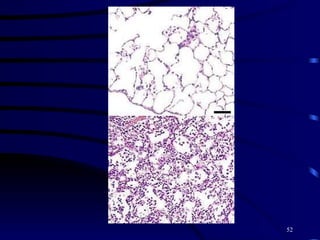

Bronchopneumonia 1.Etiology   viruses, bacteria, MP, CP.  2~3yrs old 2.pathology   edema,infiltration